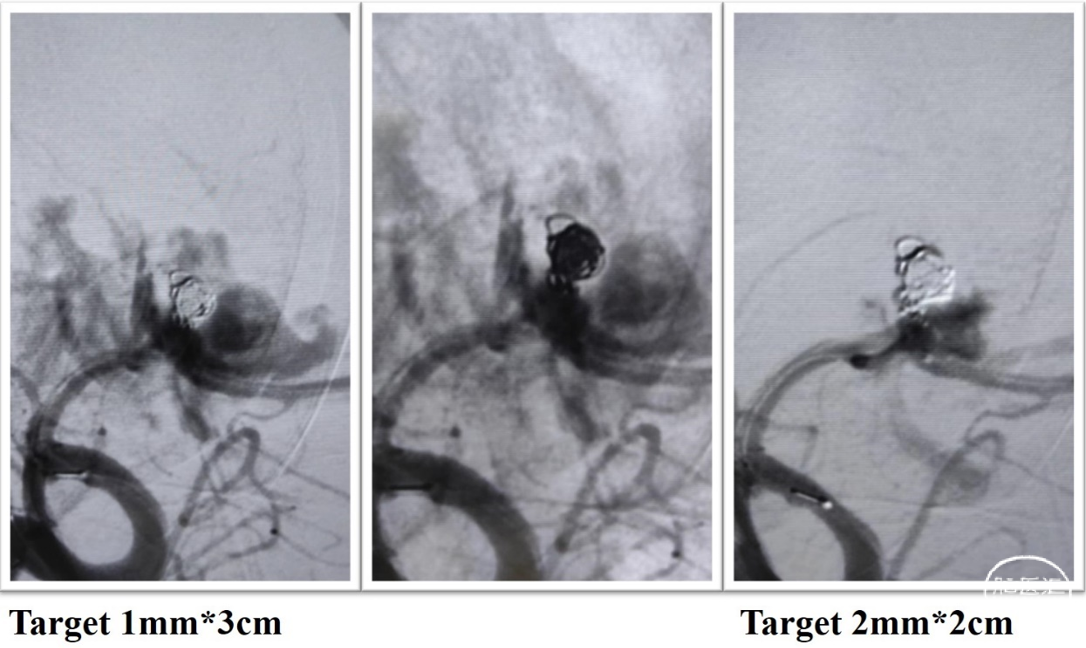

改良Seldinger法左侧股动脉置入8F动脉鞘,采用同轴技术将8F guiding置于右侧颈内动脉,在6F 115cm中间导管支撑下,微导丝Synchro 2m配合微导管SL-10进入同侧大脑前动脉A2段,另选微导管Headway17塑形后超选进入动脉瘤腔内,依次填入Target 3mm*6cm、Target 2.5mm*4cm、Microplex 2mm*4cm,造影见瘤顶部出血,尽快填入Microplex 1.5mm*3cm、Target 1mm*3cm,造影见瘤颈部撕裂造影剂外渗,再次填入Target 2mm*2cm、Target 2mm*6cm、Microplex 1.5mm*4cm、Microplex 1mm*3cm,造影见2枚动脉瘤完全栓塞,同侧大脑前动脉显影不佳,经SL-10微导管顺利释放Atlas 4mm*24mm支架,造影见支架完全覆盖瘤颈部,大脑前动脉保持通畅,终止手术。